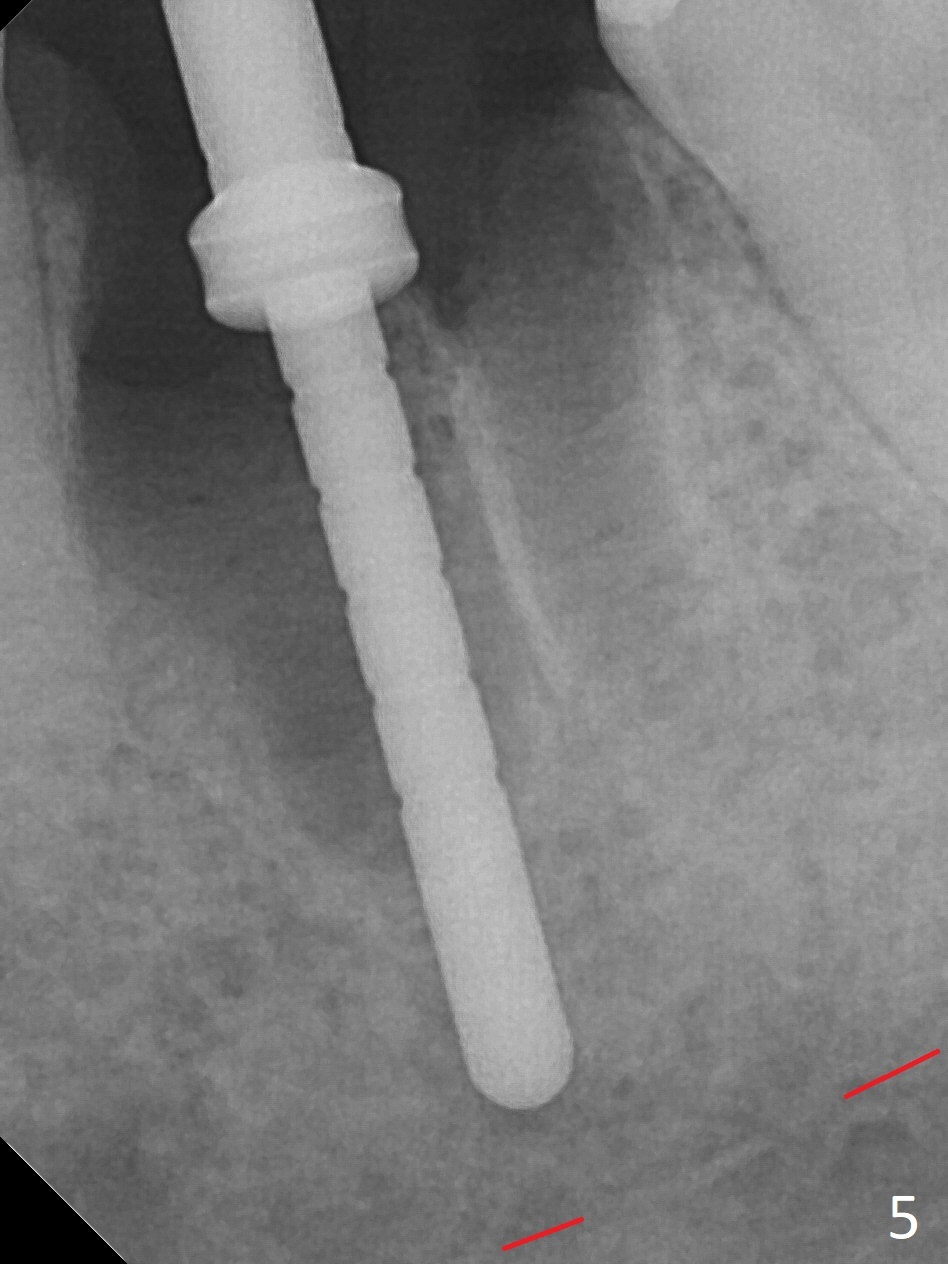

When the patient returns 9 months later, there is severe buccal gingival recession and abscess at #19 (Fig.1 *) with large mesial periradicular radiolucency (Fig.2 *).  The septum is thin and the buccal crest is low after extraction (Fig.3 * (mesial root vertical fracture)).  Osteotomy is initiated in the mesial socket immediately against the septum (Fig.4.5) with ~ 5 mm in the native bone.  Due to severe buccal plate resorption, a shorter implant is placed (Fig.6; 5x15 mm in stead of 18 mm).  There is at least 2 mm gap buccally for Vanilla Graft, which is also placed next to the implant and the neighboring root (Fig.7 *).  There is clearance from the Inferior Alveolar Canal (Fig.8 red dashed line).  Both the mesial and distal sockets heal 5.5 months postop (Fig.9), although the apical portion of the distal socket was not filled with allograft (Fig.7).  The implant was placed mesial.  The straight abutment (6.5x4(4) mm) (Fig.10) is changed to an angled one (5.5 x15 degrees 3 mm cuff (Fig.11)) before impression.  The implant is also placed buccally.  Therefore the implant position is far more important than its length.  The abutment is retightened 2.5 months post cementation, which is related to mesiobuccal placement of the implant (Fig.12).  An ideal trajectory is determined by drawing 2 horizontal lines (at crestal and apical levels: red lines in Fig.13), finding a central point of each line (vertical short line) and joining these 2 central points (Fig.14 pink line).  In fact the ideal osteotomy should have been established distal to the septum in this case.  Guided surgery may alleviate the issue.  The crown is not loose, but the patient feels that the implant tooth cannot sustain mastication.  In fact the screw is removed with hand driver (not wrench).  The abutment hex is rounded and worn.  A new 5.5x4(4) mm abutment is placed (without knowledge of previous use of an angled abutment) with mesial reduction to reduce undercut and buccodistal margin lowered to reduce gingival embrasure. It is that the straight abutment could decrease the chance of screw loosening.  Otherwise the implant has to be removed for better trajectory.